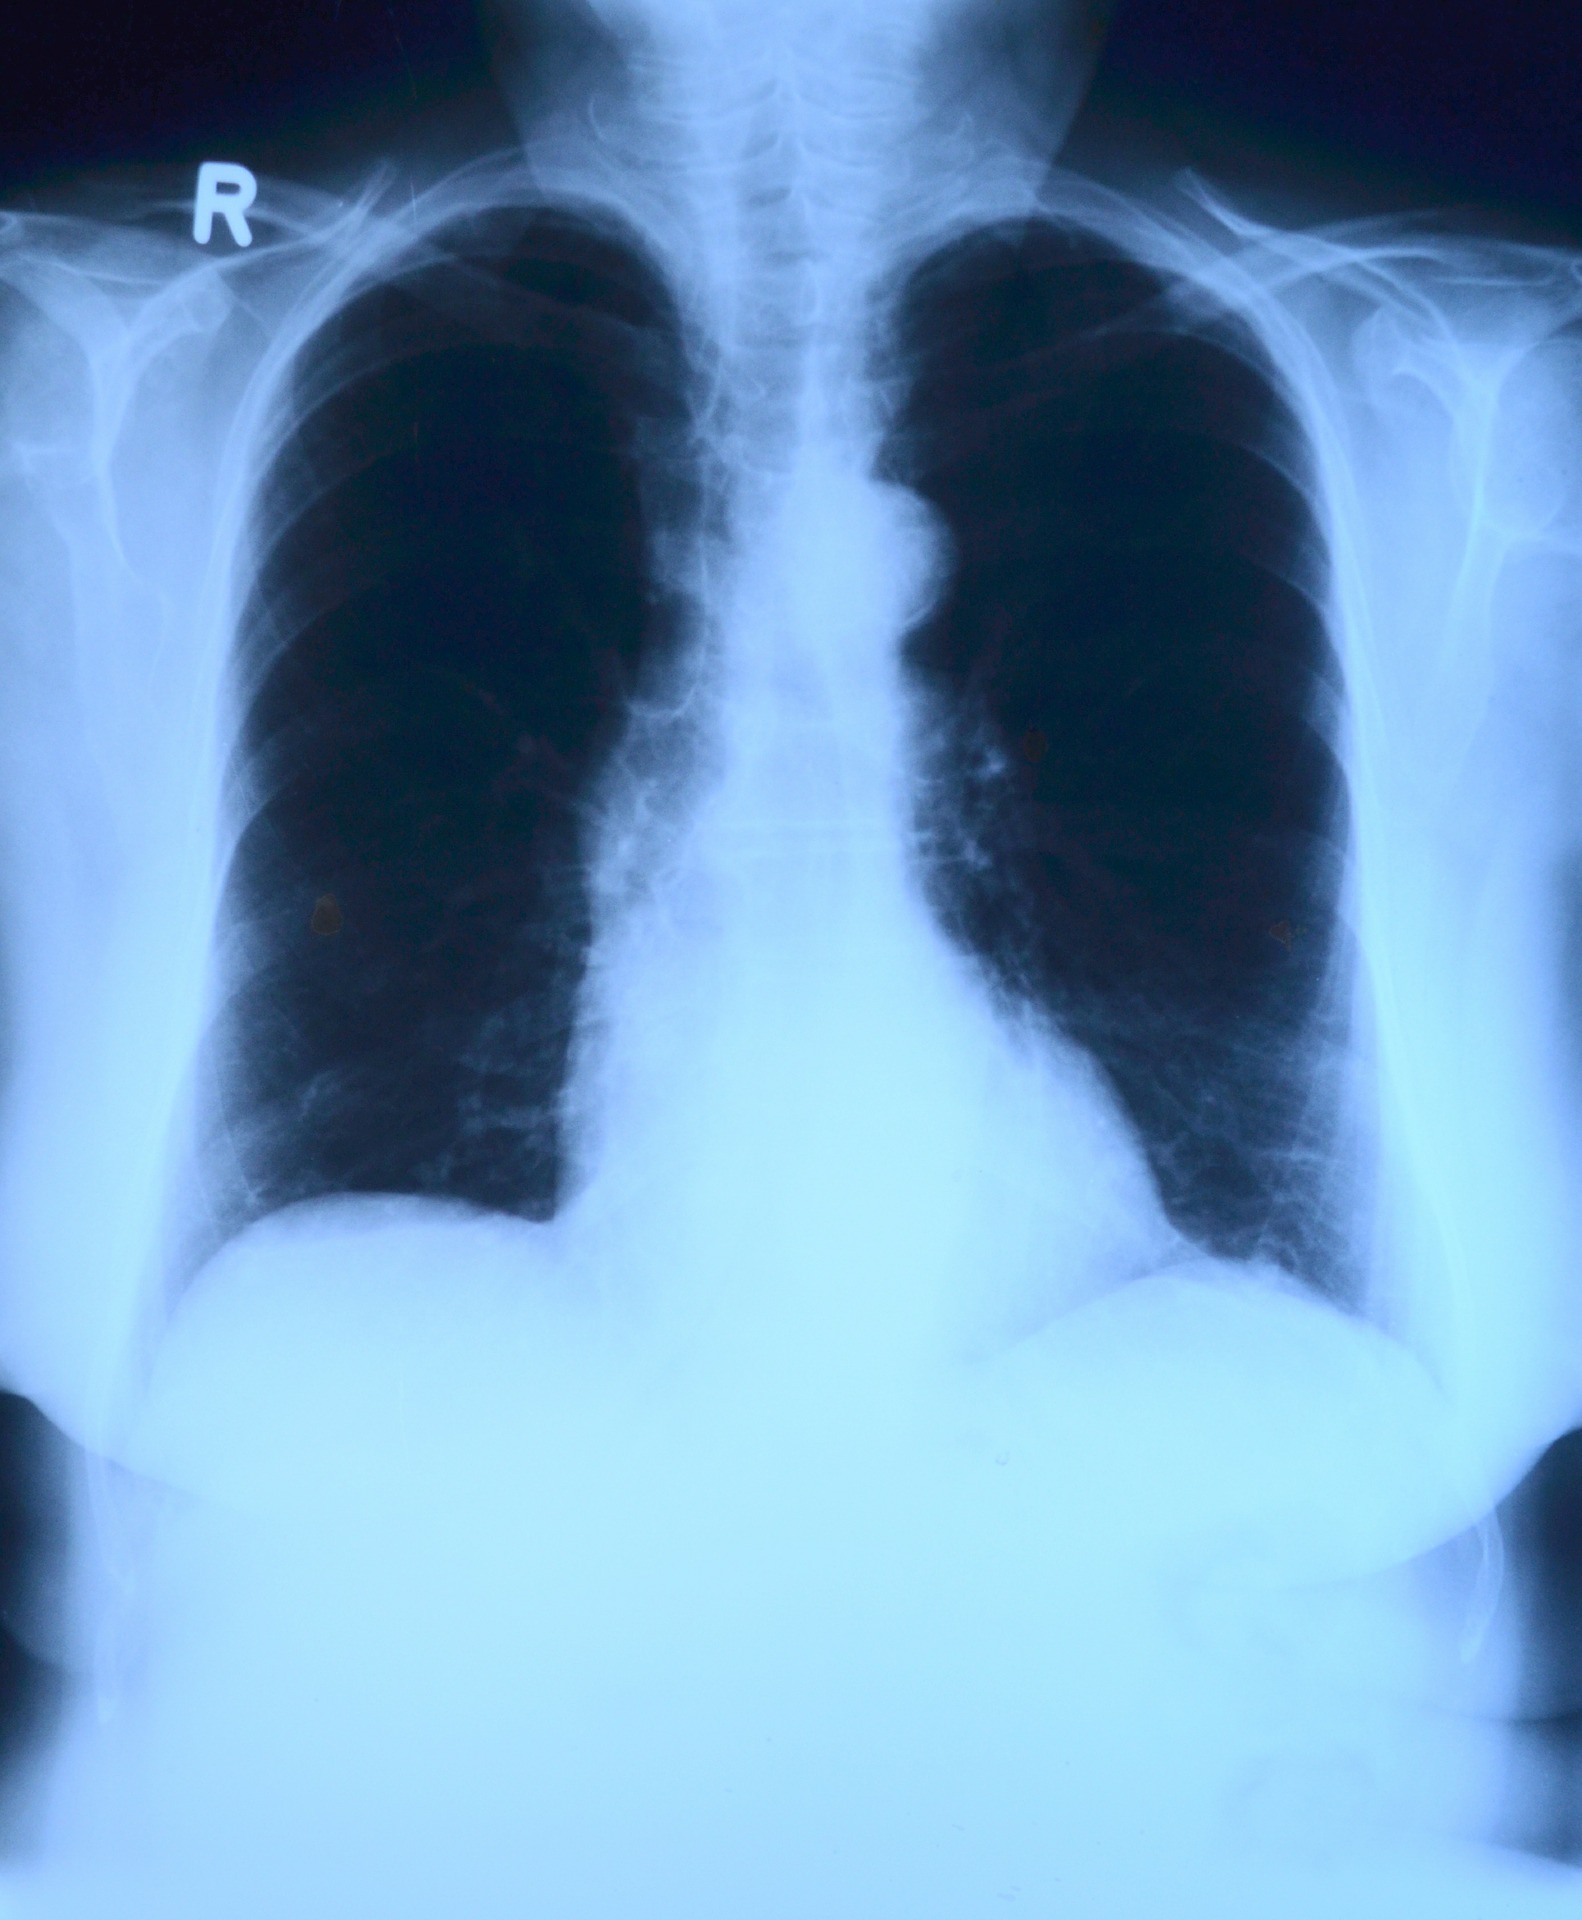

Lungebetennelse oppstår ved infeksjon i lungene, oftest av bakterier eller virus. Tilstanden kan være av både mild og alvorlig karakter. Behandlingen er ofte med medisiner, men kan forebygges med vaksine.